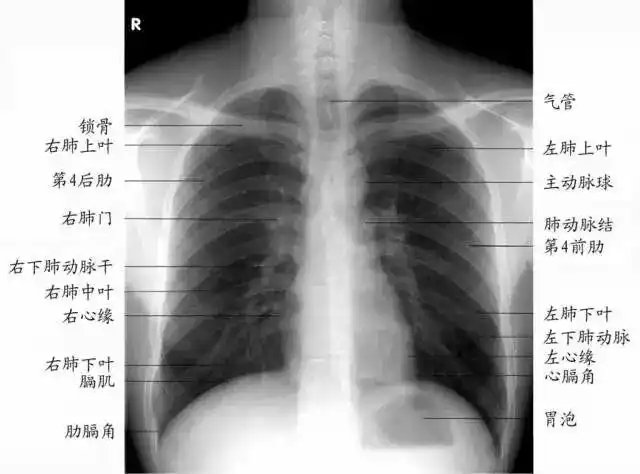

经常在x线胸片或ct检查报告中看到"两肺纹理增多增粗"这样的影像描述